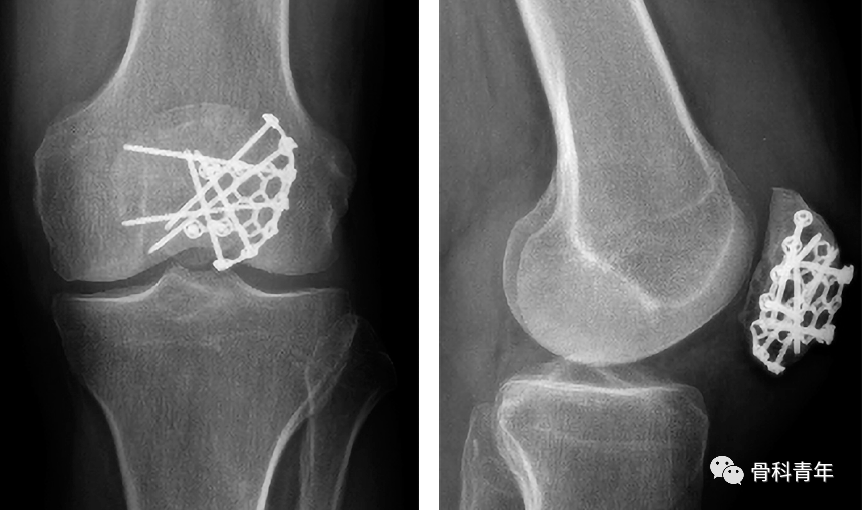

钢板固定已经成为一种新技术来解决张力带钢丝的缺点。Moore等回顾了36例C2和C3髌骨骨折患者采用前路固定角度钢板治疗的病例,他们发现有17名需要螺钉辅助固定,2名患者需辅助钢丝环扎。

Lorich等描述了9名患者,他们通过外侧关节切开术和使用允许多平面螺钉固定的新型笼形钢板进行复位。所有患者在平均23周达到愈合。只有1名患者出现需要移除的有症状植入物。未发现骨坏死、感染或伤口并发症的病例。由同一作者进行的一项前瞻性队列研究比较了25例接受相似多平面笼式固定的患者和33例接受张力带固定的患者。他们注意到,在钢板组中,大腿肌肉萎缩和膝前方疼痛明显减少。

钢板植入物通常有多个螺钉孔和锁定螺钉选项,这可能使它们更适合于粉碎骨折的固定。此外,低切迹和/或预成形以匹配髌骨独特解剖结构的设计可减少植入物突出和随后的植入物移除需要。

总之,髌骨骨折钢板固定似乎是一种有前途的技术,可治疗具有挑战性的骨折类型。